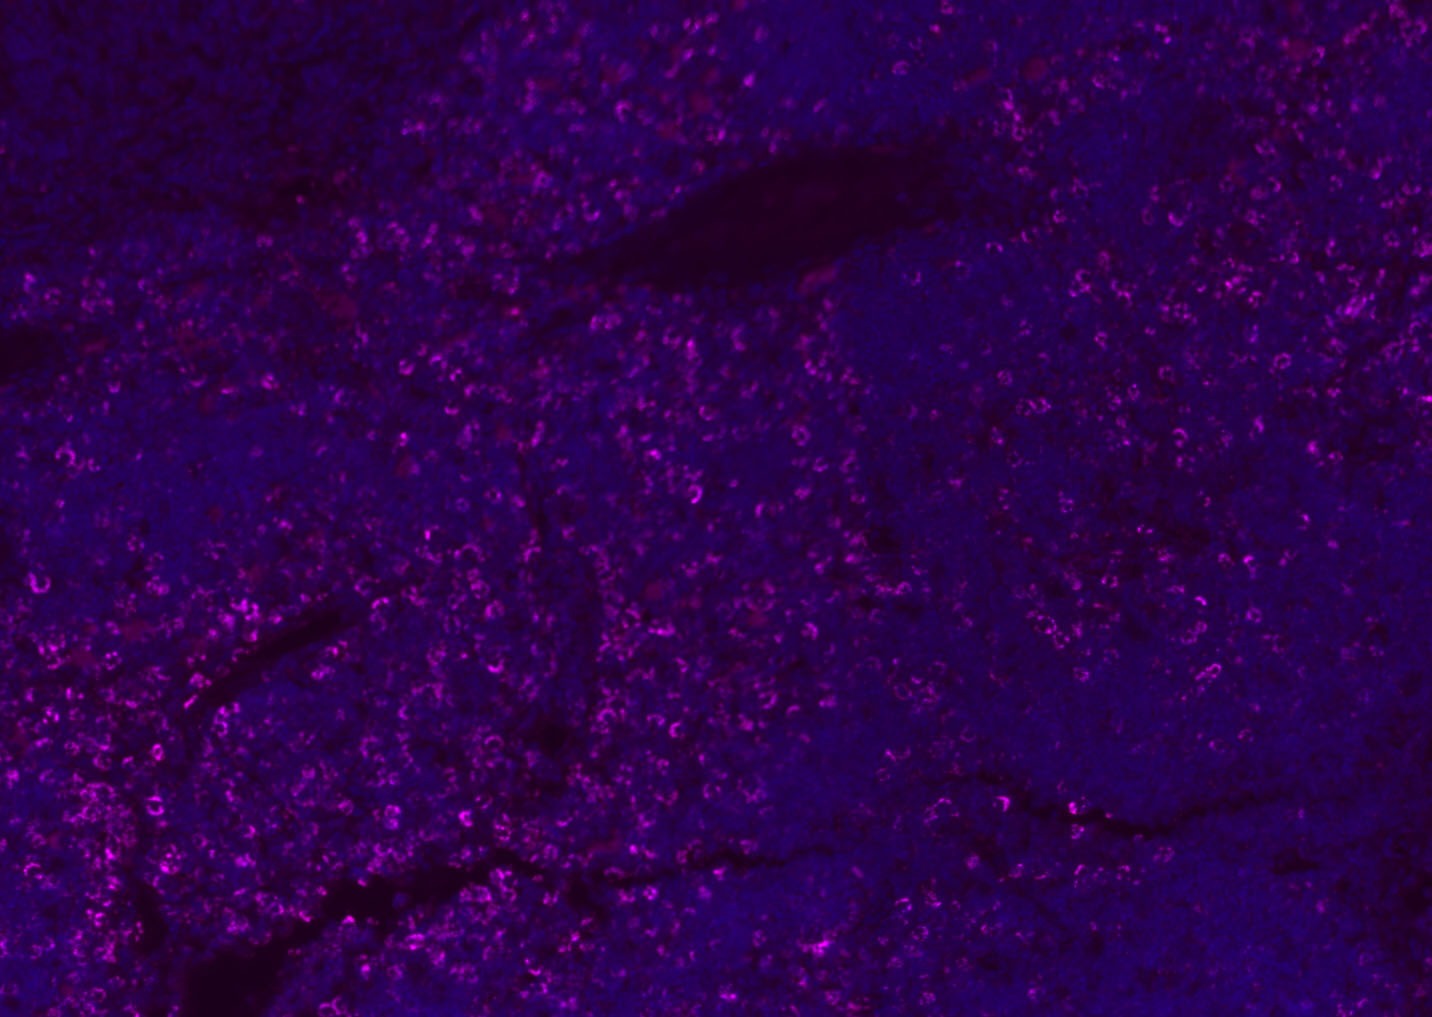

| Verified Activity | 1. Tissue/cell: human lung carcinoma;4% Paraformaldehyde-fixed and paraffin-embedded; Antigen retrieval: citrate buffer (0.01M, pH6.0), Boiling bathing for 15 min; Blocking buffer (normal goat serum) at 37°C for 20 min; Incubation: Anti-CD8 Polyclonal Antibody, Unconjugated (TMAB-00392) 1:200, overnight at 4°C; The secondary antibody was Goat Anti-Rabbit IgG, Cy3 conjugated used at 1:200 dilution for 40 minutes at 37°C. DAPI (5 μg/ml,blue) was used to stain the cell nucleus. 2. Paraformaldehyde-fixed, paraffin embedded (mouse lymphoid); Antigen retrieval by boiling in sodium citrate buffer (pH6.0) for 15 min; Blocking buffer (normal goat serum) at 37°C for 30 min; Antibody incubation with (CD8B) Polyclonal Antibody, Unconjugated (TMAB-00392) at 1:200 overnight at 4°C, followed by a conjugated Goat Anti-Rabbit IgG antibody for 90 minutes, and DAPI for nucleus staining. 3. Paraformaldehyde-fixed, paraffin embedded (rat spleen); Antigen retrieval by boiling in sodium citrate buffer (pH6.0) for 15 min; Blocking buffer (normal goat serum) at 37°C for 30 min; Antibody incubation with (CD8B) Polyclonal Antibody, Unconjugated (TMAB-00392) at 1:200 overnight at 4°C, followed by a conjugated Goat Anti-Rabbit IgG antibody for 90 minutes, and DAPI for nucleus staining. 4. Paraformaldehyde-fixed, paraffin embedded (mouse thymus); Antigen retrieval by boiling in sodium citrate buffer (pH6.0) for 15 min; Blocking buffer (normal goat serum) at 37°C for 30 min; Antibody incubation with (CD8B) Polyclonal Antibody, Unconjugated (TMAB-00392) at 1:200 overnight at 4°C, followed by a conjugated Goat Anti-Rabbit IgG antibody for 90 minutes, and DAPI for nucleus staining. 5. Paraformaldehyde-fixed, paraffin embedded (rat lymphoid); Antigen retrieval by boiling in sodium citrate buffer (pH6.0) for 15 min; Blocking buffer (normal goat serum) at 37°C for 30 min; Antibody incubation with (CD8B) Polyclonal Antibody, Unconjugated (TMAB-00392) at 1:200 overnight at 4°C, followed by a conjugated Goat Anti-Rabbit IgG antibody for 90 minutes, and DAPI for nucleus staining. 6. Paraformaldehyde-fixed, paraffin embedded (rat thymus); Antigen retrieval by boiling in sodium citrate buffer (pH6.0) for 15 min; Blocking buffer (normal goat serum) at 37°C for 30 min; Antibody incubation with (CD8B) Polyclonal Antibody, Unconjugated (TMAB-00392) at 1:200 overnight at 4°C, followed by a conjugated Goat Anti-Rabbit IgG antibody for 90 minutes, and DAPI for nucleus staining. 7. Paraformaldehyde-fixed, paraffin embedded (human tonsil); Antigen retrieval by boiling in sodium citrate buffer (pH6.0) for 15 min; Blocking buffer (normal goat serum) at 37°C for 30 min; Antibody incubation with (CD8B) Polyclonal Antibody, Unconjugated (TMAB-00392) at 1:200 overnight at 4°C, followed by a conjugated Goat Anti-Rabbit IgG antibody for 90 minutes, and DAPI for nucleus staining. 8. Paraformaldehyde-fixed, paraffin embedded (mouse lymphoid); Antigen retrieval by boiling in sodium citrate buffer (pH6.0) for 15 min; Blocking buffer (normal goat serum) at 37°C for 30 min; Antibody incubation with (CD8B) Polyclonal Antibody, Unconjugated (TMAB-00392) at 1:200 overnight at 4°C, followed by a conjugated Goat Anti-Rabbit IgG antibody for 90 minutes, and DAPI for nucleus staining. 9. Paraformaldehyde-fixed, paraffin embedded (rat thymus); Antigen retrieval by boiling in sodium citrate buffer (pH6.0) for 15 min; Blocking buffer (normal goat serum) at 37°C for 30 min; Antibody incubation with (CD8B) Polyclonal Antibody, Unconjugated (TMAB-00392) at 1:200 overnight at 4°C, followed by a conjugated Goat Anti-Rabbit IgG antibody for 90 minutes, and DAPI for nucleus staining. 10. Paraformaldehyde-fixed, paraffin embedded (human tonsil); Antigen retrieval by boiling in sodium citrate buffer (pH6.0) for 15 min; Blocking buffer (normal goat serum) at 37°C for 30 min; Antibody incubation with (CD8B) Polyclonal Antibody, Unconjugated (TMAB-00392) at 1:200 overnight at 4°C, followed by a conjugated Goat Anti-Rabbit IgG antibody for 90 minutes, and DAPI for nucleus staining. 11. Paraformaldehyde-fixed, paraffin embedded (mouse spleen); Antigen retrieval by boiling in sodium citrate buffer (pH6.0) for 15 min; Blocking buffer (normal goat serum) at 37°C for 30 min; Antibody incubation with (CD8B) Polyclonal Antibody, Unconjugated (TMAB-00392) at 1:200 overnight at 4°C, followed by a conjugated Goat Anti-Rabbit IgG antibody for 90 minutes, and DAPI for nucleus staining. 12. Paraformaldehyde-fixed, paraffin embedded (rat lymphoid); Antigen retrieval by boiling in sodium citrate buffer (pH6.0) for 15 min; Blocking buffer (normal goat serum) at 37°C for 30 min; Antibody incubation with (CD8B) Polyclonal Antibody, Unconjugated (TMAB-00392) at 1:200 overnight at 4°C, followed by a conjugated Goat Anti-Rabbit IgG antibody for 90 minutes, and DAPI for nucleus staining. 13. Paraformaldehyde-fixed, paraffin embedded (Rat lymphoid); Antigen retrieval by boiling in sodium citrate buffer (pH6.0) for 15 min; Blocking buffer (normal goat serum) at 37°C for 30 min; Antibody incubation with (CD8B) Polyclonal Antibody, Unconjugated (TMAB-00392) at 1:100 overnight at 4°C, followed by a conjugated Goat Anti-Rabbit IgG antibody for 90 minutes, and DAPI for nucleus staining. 14. Paraformaldehyde-fixed, paraffin embedded (mouse thymus); Antigen retrieval by boiling in sodium citrate buffer (pH6.0) for 15 min; Blocking buffer (normal goat serum) at 37°C for 30 min; Antibody incubation with (CD8B) Polyclonal Antibody, Unconjugated (TMAB-00392) at 1:100 overnight at 4°C, followed by a conjugated Goat Anti-Rabbit IgG antibody for 90 minutes, and DAPI for nucleus staining. 15. Paraformaldehyde-fixed, paraffin embedded (mouse spleen); Antigen retrieval by boiling in sodium citrate buffer (pH6.0) for 15 min; Blocking buffer (normal goat serum) at 37°C for 30 min; Antibody incubation with (CD8B) Polyclonal Antibody, Unconjugated (TMAB-00392) at 1:100 overnight at 4°C, followed by a conjugated Goat Anti-Rabbit IgG antibody for 90 minutes, and DAPI for nucleus staining. 16. Paraformaldehyde-fixed, paraffin embedded (rat spleen); Antigen retrieval by boiling in sodium citrate buffer (pH6.0) for 15 min; Blocking buffer (normal goat serum) at 37°C for 30 min; Antibody incubation with (CD8B) Polyclonal Antibody, Unconjugated (TMAB-00392) at 1:100 overnight at 4°C, followed by a conjugated Goat Anti-Rabbit IgG antibody for 90 minutes, and DAPI for nucleus staining. 17. Paraformaldehyde-fixed, paraffin embedded (rat thymus); Antigen retrieval by boiling in sodium citrate buffer (pH6.0) for 15 min; Blocking buffer (normal goat serum) at 37°C for 30 min; Antibody incubation with (CD8B) Polyclonal Antibody, Unconjugated (TMAB-00392) at 1:100 overnight at 4°C, followed by a conjugated Goat Anti-Rabbit IgG antibody for 90 minutes, and DAPI for nucleus staining. 18. Paraformaldehyde-fixed, paraffin embedded (human tonsil); Antigen retrieval by boiling in sodium citrate buffer (pH6.0) for 15 min; Blocking buffer (normal goat serum) at 37°C for 30 min; Antibody incubation with (CD8B) Polyclonal Antibody, Unconjugated (TMAB-00392) at 1:100 overnight at 4°C, followed by a conjugated Goat Anti-Rabbit IgG antibody for 90 minutes, and DAPI for nucleus staining. 19. Paraformaldehyde-fixed, paraffin embedded (mouse lymphoid); Antigen retrieval by boiling in sodium citrate buffer (pH6.0) for 15 min; Blocking buffer (normal goat serum) at 37°C for 30 min; Antibody incubation with (CD8B) Polyclonal Antibody, Unconjugated (TMAB-00392) at 1:100 overnight at 4°C, followed by a conjugated Goat Anti-Rabbit IgG antibody for 90 minutes, and DAPI for nucleus staining. ![]() ![]() ![]() ![]() ![]() ![]() ![]() ![]() ![]() ![]() ![]() ![]() ![]() ![]() ![]() ![]() ![]() ![]() ![]() |